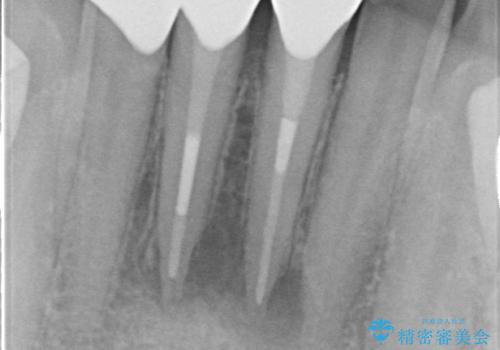

- 歯がない左側でものが咬めず、右側で咬むと歯が痛むので診て欲しいといらっしゃった方の症例です。

根尖病変が認められる歯は再根管治療を行い、歯根が破折していた左上4は抜歯しました。

インプラントは希望されなかったため、左側は1番から7番のロングスパンブリッジによる補綴を行いました。